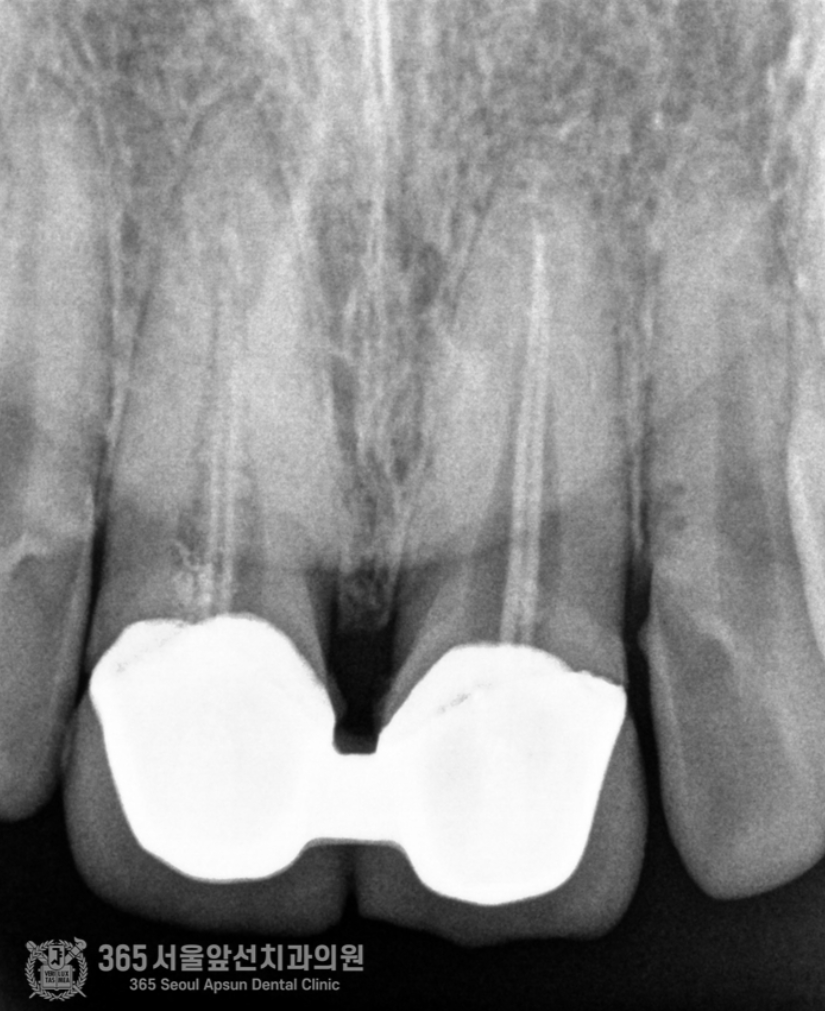

위쪽 앞니 보철물을 한지 오래됐는데, 바꾸고 싶어요. 안녕하세요. 주안역치과 365서울앞선치과 대표원장 강동우입니다. 오늘 소개해드릴 치료 증례는 앞니 보철물이 어색하다는 불편감으로 내원하신 환자분의 증례입니다~ 앞니는 치아의 기능도 중요하지만 무엇보다 심미성이 중요합니다. 쉽게 말해 앞니는 이쁜게 중요하다고 볼 수 있습니다 ㅎㅎ 촬영일시 : 2024.05.03. 처음 내원 당시 정면 모습입니다. 환자분께서 나이가 젊으셨음에도 불구하고 앞니의 보철물의 색상이 탁하고 어두워보이며 심지어 앞니 끝부분이 깨져있는것도 보입니다. 또한 PFM이라고 내부에 금속구조물을 포함한 보철물이다보니 금속 구조물이 빛의 투과를 막아 잇몸색이 탁한 색으로 보이는 우산효과(umbrella effect)도 관찰됩니다. 촬영일시 : 2024.05.03. 내원 당시 치료전 엑스레이입니다. PFM으로 제작된 앞니 보철물이 관찰되며, 치아 내부에 신경치료가 행해졌던 흔적도 보입니다. 환자분께서 증상은 따로 없으셨으나, 신경치료 상태가 불량하여 재신경치료도 진행하기로 했습니다. 촬영일시 : 2024.05.03. 재신경치료 중에 촬영한 엑스레이입니다. 정확하게 신경치료가 이루어지고있는것이 관찰됩니다. 촬영일시 : 2024.05.03. 재신경치료 후 엑스레이 사진입니다. 깔끔하게 충전된 양상이 관찰됩니다. 촬영일시 : 2024.05.03. / 2025.08.02. 이제 심미의 완성을 위한 잠정보철물(Provisional restoration)을 제작하여 환자분께서 원하는 형태를 찾아가며, 잇몸의 형태도 조절하는 과정(gingival molding)을 진행합니다. 환자분께서 심미를 중요시 여기는 분이셔서 두 번에 걸친 임시치아 제작 단계를 거쳐 최종적인 보철물을 만들었습니다. 촬영일시 : 2025.08.02. 완성된 최종보철물입니다. 깔끔하게 잘나왔습니다 어두웠던 잇몸색상도 개선되었습니다. 환자분께서도 만족하셨습니다 ㅎㅎ 촬영일시 : 2024.05.03. / 2025.08.02. 치료 전후 비교 모습입니다. 드라마틱한 변화가 관찰됩니다. 오늘은 오래된 앞니 보철물 교체에 관한 주제로 증례를 소개해드렸습니다. 앞으로도 좋은 치료로 보답하는 석바위시장치과, 365서울앞선치과가 되겠습니다 ! [ 치료기간: 2024년 5월3일 ~2025년 8월 2일 ] ※ 365서울앞선치과의원의 모든 포스팅은 각 진료과 의료진이 직접 작성합니다. 365서울앞선치과의원 블로그의 임상 케이스 게시물은 환자분께 의학적으로 정확하고 상세한 정보를 드리기 위해 각 진료과 의료진이 직접 작성하며, 모든 증례 사진은 본원 의료진이 직접 시술한 증례를 촬영한 것으로, 의료법 제23조, 제56조에 의거하며 환자분의 동의를 얻어 포스팅에 사용하였습니다. 또한 해당 케이스는 본 환자분의 치료 결과이며, 환자 상태에 따라 치료의 결과는 달라질 수 있습니다. |